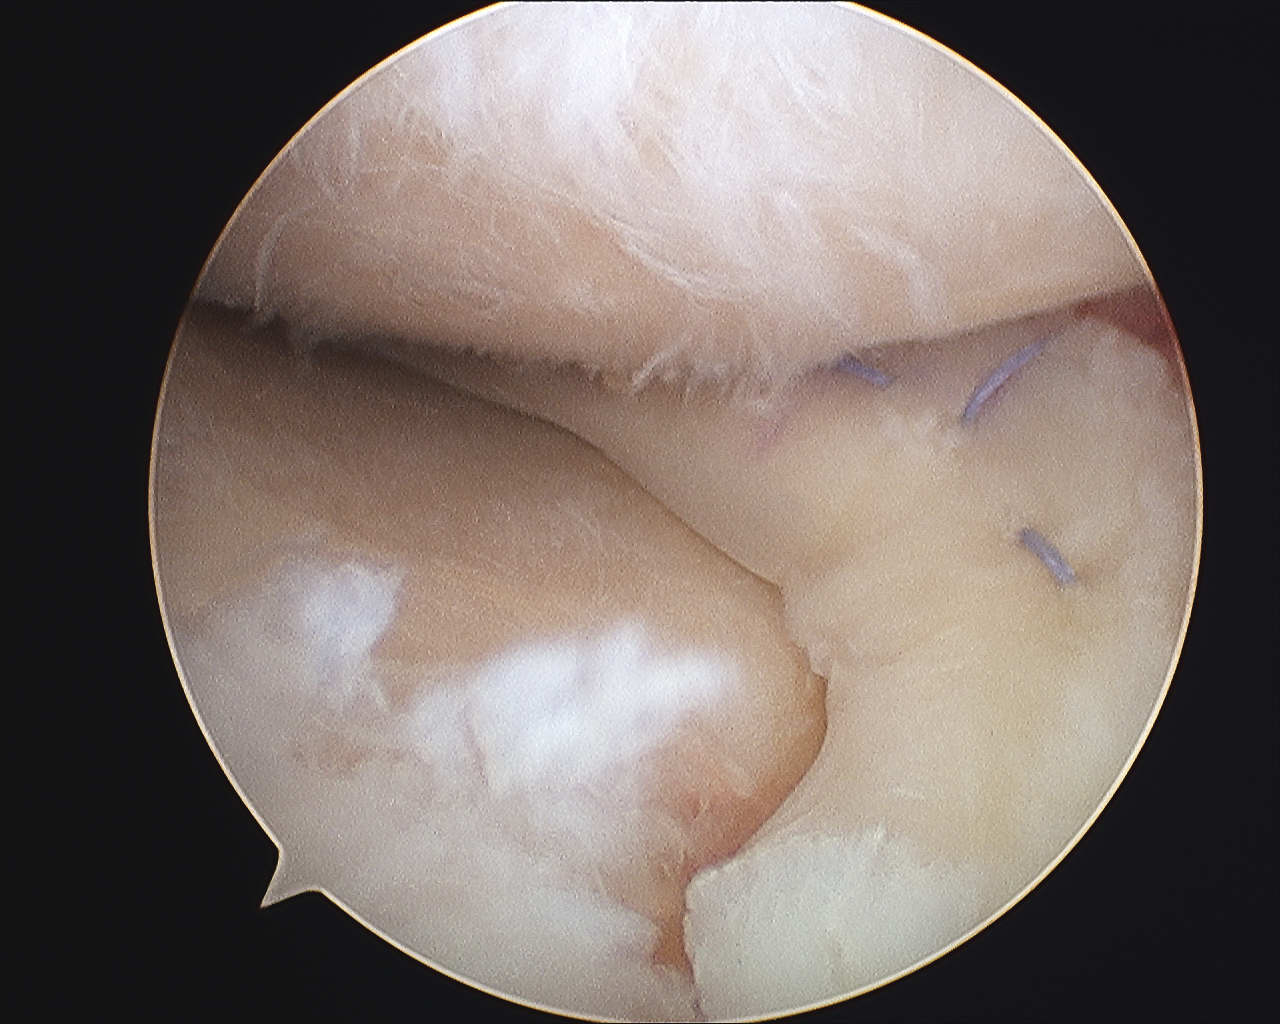

A medial meniscus transplantation was performed.